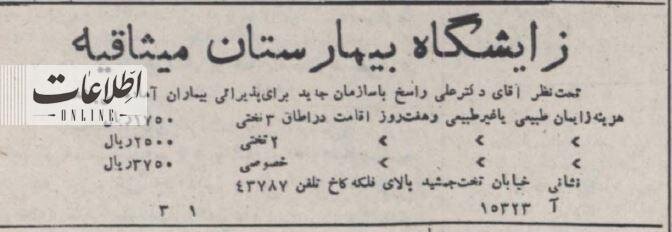

۷۰ سال پیش هزینه زایمان در تهران چقدر بود؟/ عکسی از اتاق زایمان

در سال ۱۳۳۲ بیمارستان میثاقیه (مصطفی خمینی (ره)) تهران یک مرکز درمانی خصوصی بود که در خیابان اعیان نشین کاخ (فلسطین) قرار داشت. این بیمارستان ۷۰ سال پیش بخش زایمان خود را راه اندازی و برای اطلاع رسانی آگهی در روزنامه اطلاعات ۷ بهمن ۱۳۳۲ منتشر کرد. آگهی را بخوانید و عکسی از یک اتاق زایشگاه میثاقیه در همان سالها را تماشا کنید. هزینه زایمان با هفت روز اقامت در اتاق سه تخته ۱۷۵ تومان، دو تخته ۲۵۰ و خصوصی ۳۷۵ تومان بوده است.